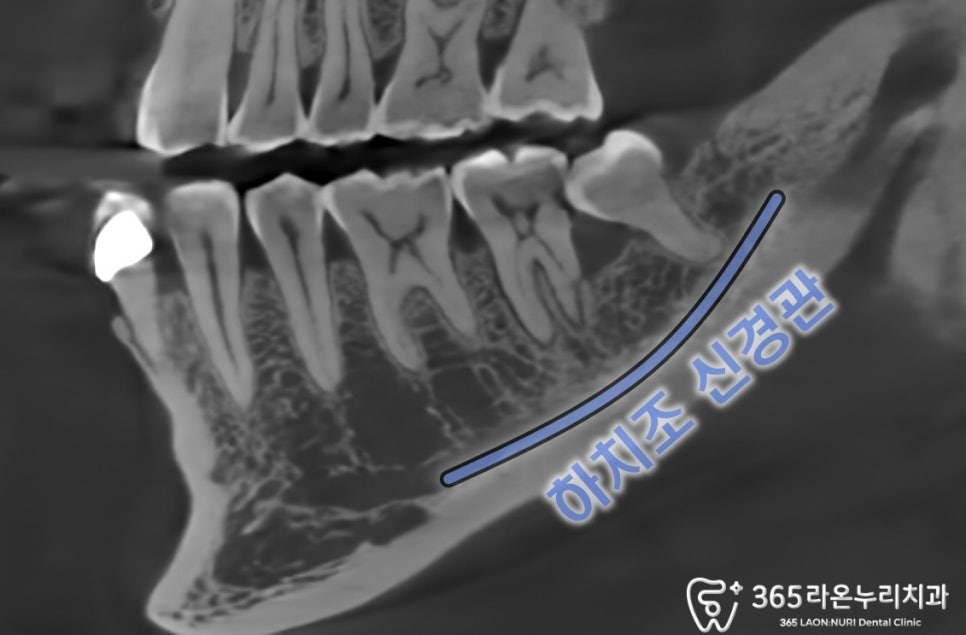

발치를 결정했다면

CT를 찍어 신경관과 관계를 봐야됩니다.

하악 어금니 아래쪽에는

하치조신경이 지나고 있어

더욱 신중한 발치 과정이

필요합니다.

또 CT를 자세히 보면

47번 치아의 치근파절이 된 모습을

살펴볼 수 있었습니다.